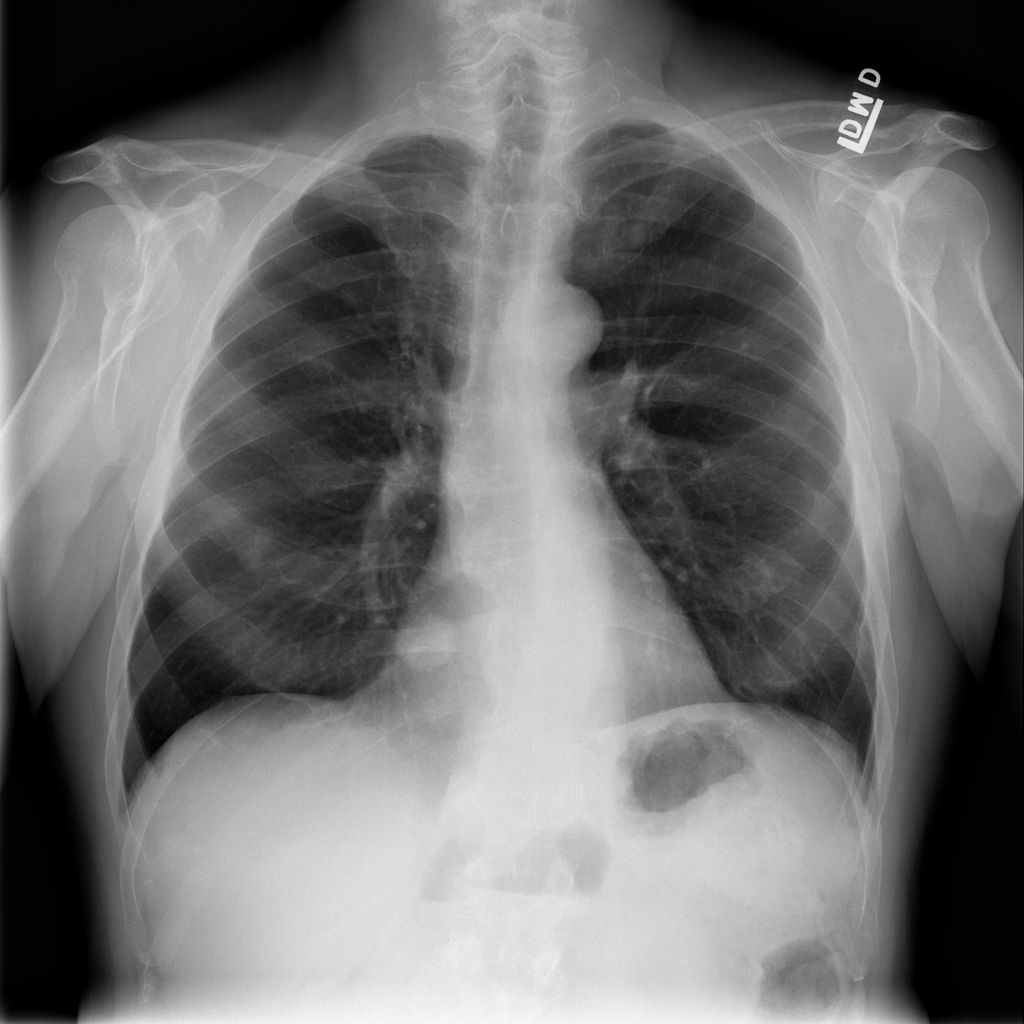

PAT-50E5 · IMG-000Nodule

PAT-50E5 · IMG-000

PA